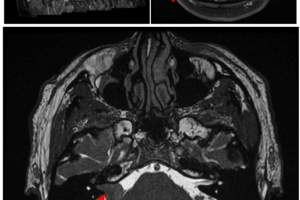

Posterior Fossa Metastasis

The differential diagnosis for an intra-axial posterior fossa mass depends on the age of the patient. The most common causes are juvenile pilocytic astrocytoma, medulloblastoma and ependymoma in a child and metastasis... Read more »